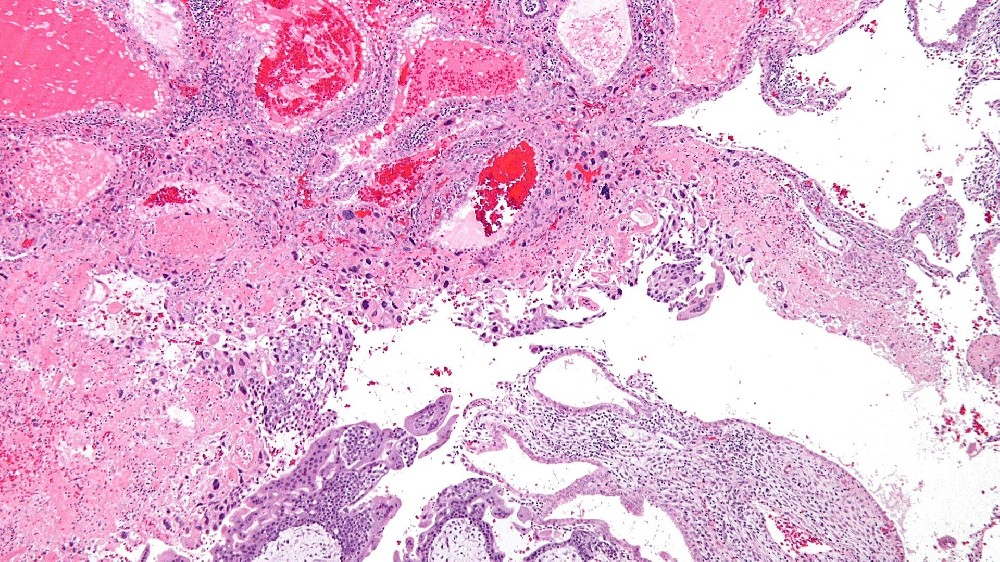

妊娠滋養細胞疾病 (Gestational Trophoblastic Disease, GTD) 是一種罕見的腫瘤,源自胎盤組織,特別是滋養細胞。滋養層細胞通常在懷孕期間發育成胎盤,幫助滋養胚胎。然而,滋養母細胞的異常可導致不受控制的生長,形成腫瘤或囊腫,並啟動妊娠滋養細胞疾病 (GTD)。

在全球範圍內,每 1,000 名孕婦中約有 1 例發生妊娠滋養細胞疾病 (GTD),其亞型各異,包括水滴形痣 (包括完全性和部分性)、浸润性痣、絨毛膜癌和胎盤部位滋養細胞瘤。然而,地區性的差異很普遍,特別是在香港和亞洲其他地區,GTD的發生率較高。

雖然與 GTD 有明顯關聯的特定遺傳基因非常罕見,但基因組研究突顯了與 GTD 亞型相關的染色體異常。例如,完全水滴形痣通常是由父系基因組重複所造成 (46XX 核型,完全源自父系)。相反地,部分水滴形痣通常會顯示三倍核型 (69 條染色體),混合母源與父源。

值得注意的是,GTD 細胞對葡萄糖攝取的異常依賴,代表了針對性治療的主要新陳代謝弱點。這些滋養細胞具有類似 Warburg 效應的特徵,會快速大量消耗葡萄糖,加速細胞生長並促進惡性發展。